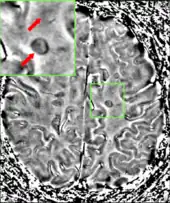

Multiple sclerosis as seen on MRI

Clinical data alone may be sufficient for a diagnosis of MS if an individual has had separate episodes of neurological symptoms characteristic of the disease.[54] In those who seek medical attention after only one attack, other testing is needed for the diagnosis. The most commonly used diagnostic tools are neuroimaging, analysis of cerebrospinal fluid and evoked potentials. Magnetic resonance imaging of the brain and spine may show areas of demyelination (lesions or plaques). Gadolinium can be administered intravenously as a contrast agent to highlight active plaques and, by elimination, demonstrate the existence of historical lesions not associated with symptoms at the moment of the evaluation.[54][55] Testing of cerebrospinal fluid obtained from a lumbar puncture can provide evidence of chronic inflammation in the central nervous system. The cerebrospinal fluid is tested for oligoclonal bands of IgG on electrophoresis, which are inflammation markers found in 75–85% of people with MS.[54][56] The nervous system in MS may respond less actively to stimulation of the optic nerve and sensory nerves due to demyelination of such pathways. These brain responses can be examined using visual- and sensory-evoked potentials.[57]